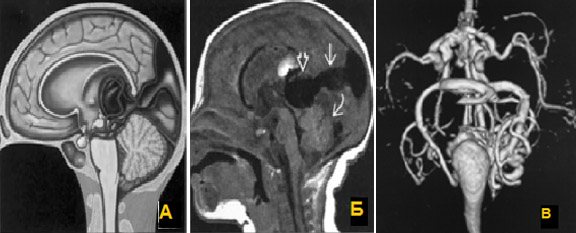

Мальформация большой вены мозга (вены Галена).

Центрально расположенная АВМ, дренирующаяся в вену Галена, с формированием ее варикозного расширения. У новорожденных могут возникать явления сердечной недостаточности за счет большого объема шунтового кровотока.

а) Мальформация (варикозное расширение) вены Галена, схема. б)Т1-sag определяется расширенная вена Галена (открытая стрелка), дренирующаяся (стрелка) в сагиттальный синус; в) МР-объемная реконструкция.